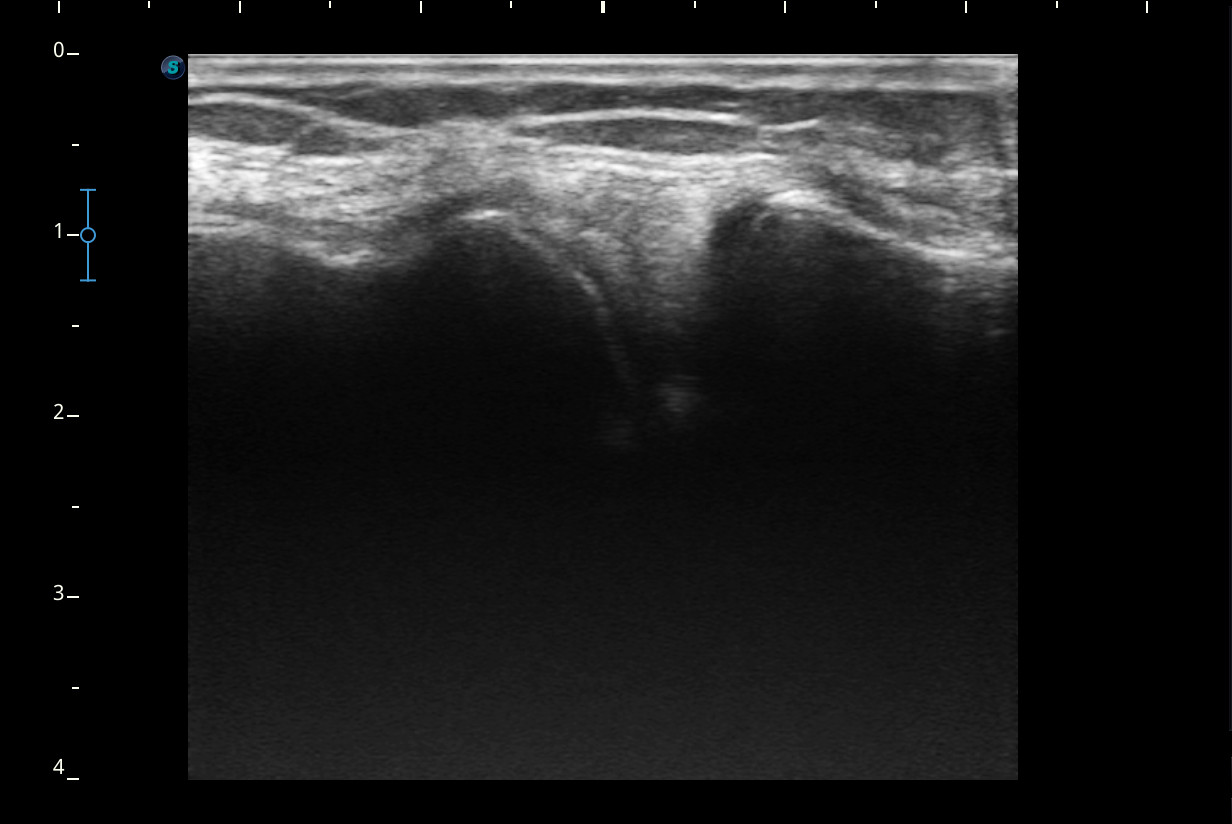

Rodilla sin derrame articular. No se aprecian lesiones en Ligamentos colaterales. Ligamento rotuliano sin hallazgos valorables. Rotura menisco interno y dudosa fisura menisco externo. Tendones rotuliano y cuadricipital normales.

Resonancia magnética confirma rotura cuerno posterior menisco interno.

Rotura cuerno posterior menisco interno.